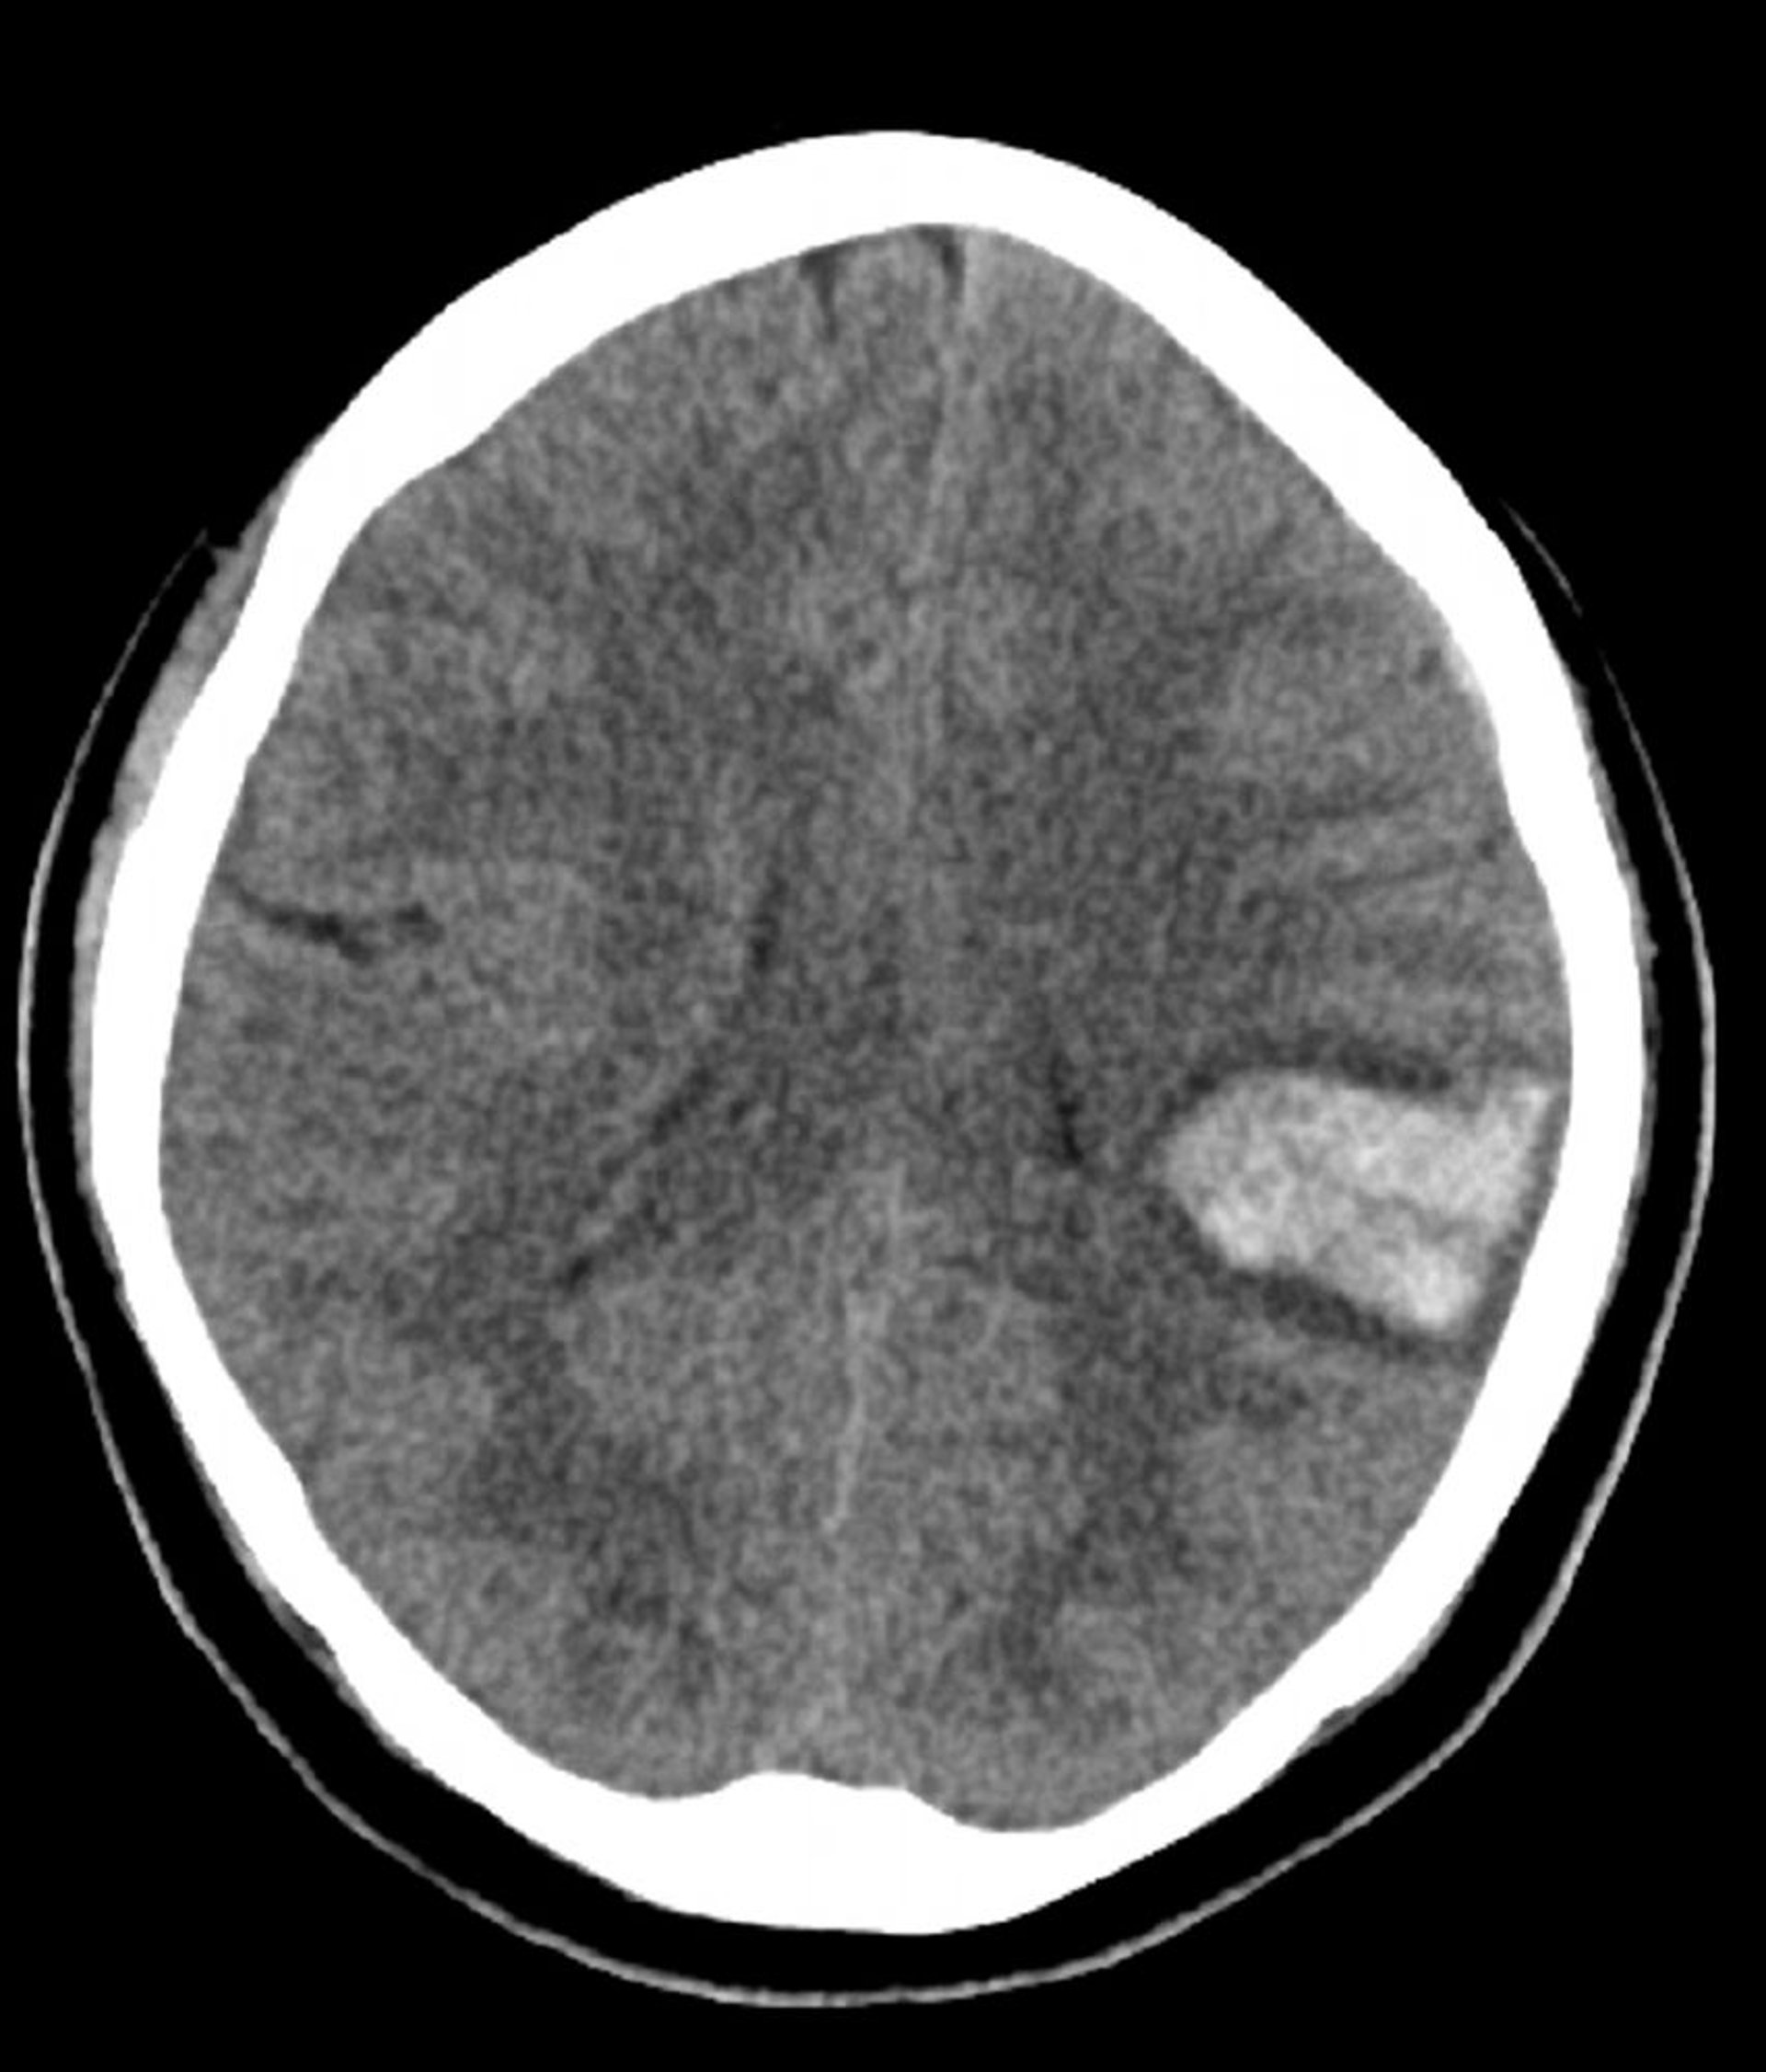

Hemorragia intracerebral

El aumento de la densidad en el cerebro izquierdo que se observa en esta TC sin contraste es compatible con una hemorragia intracerebral.